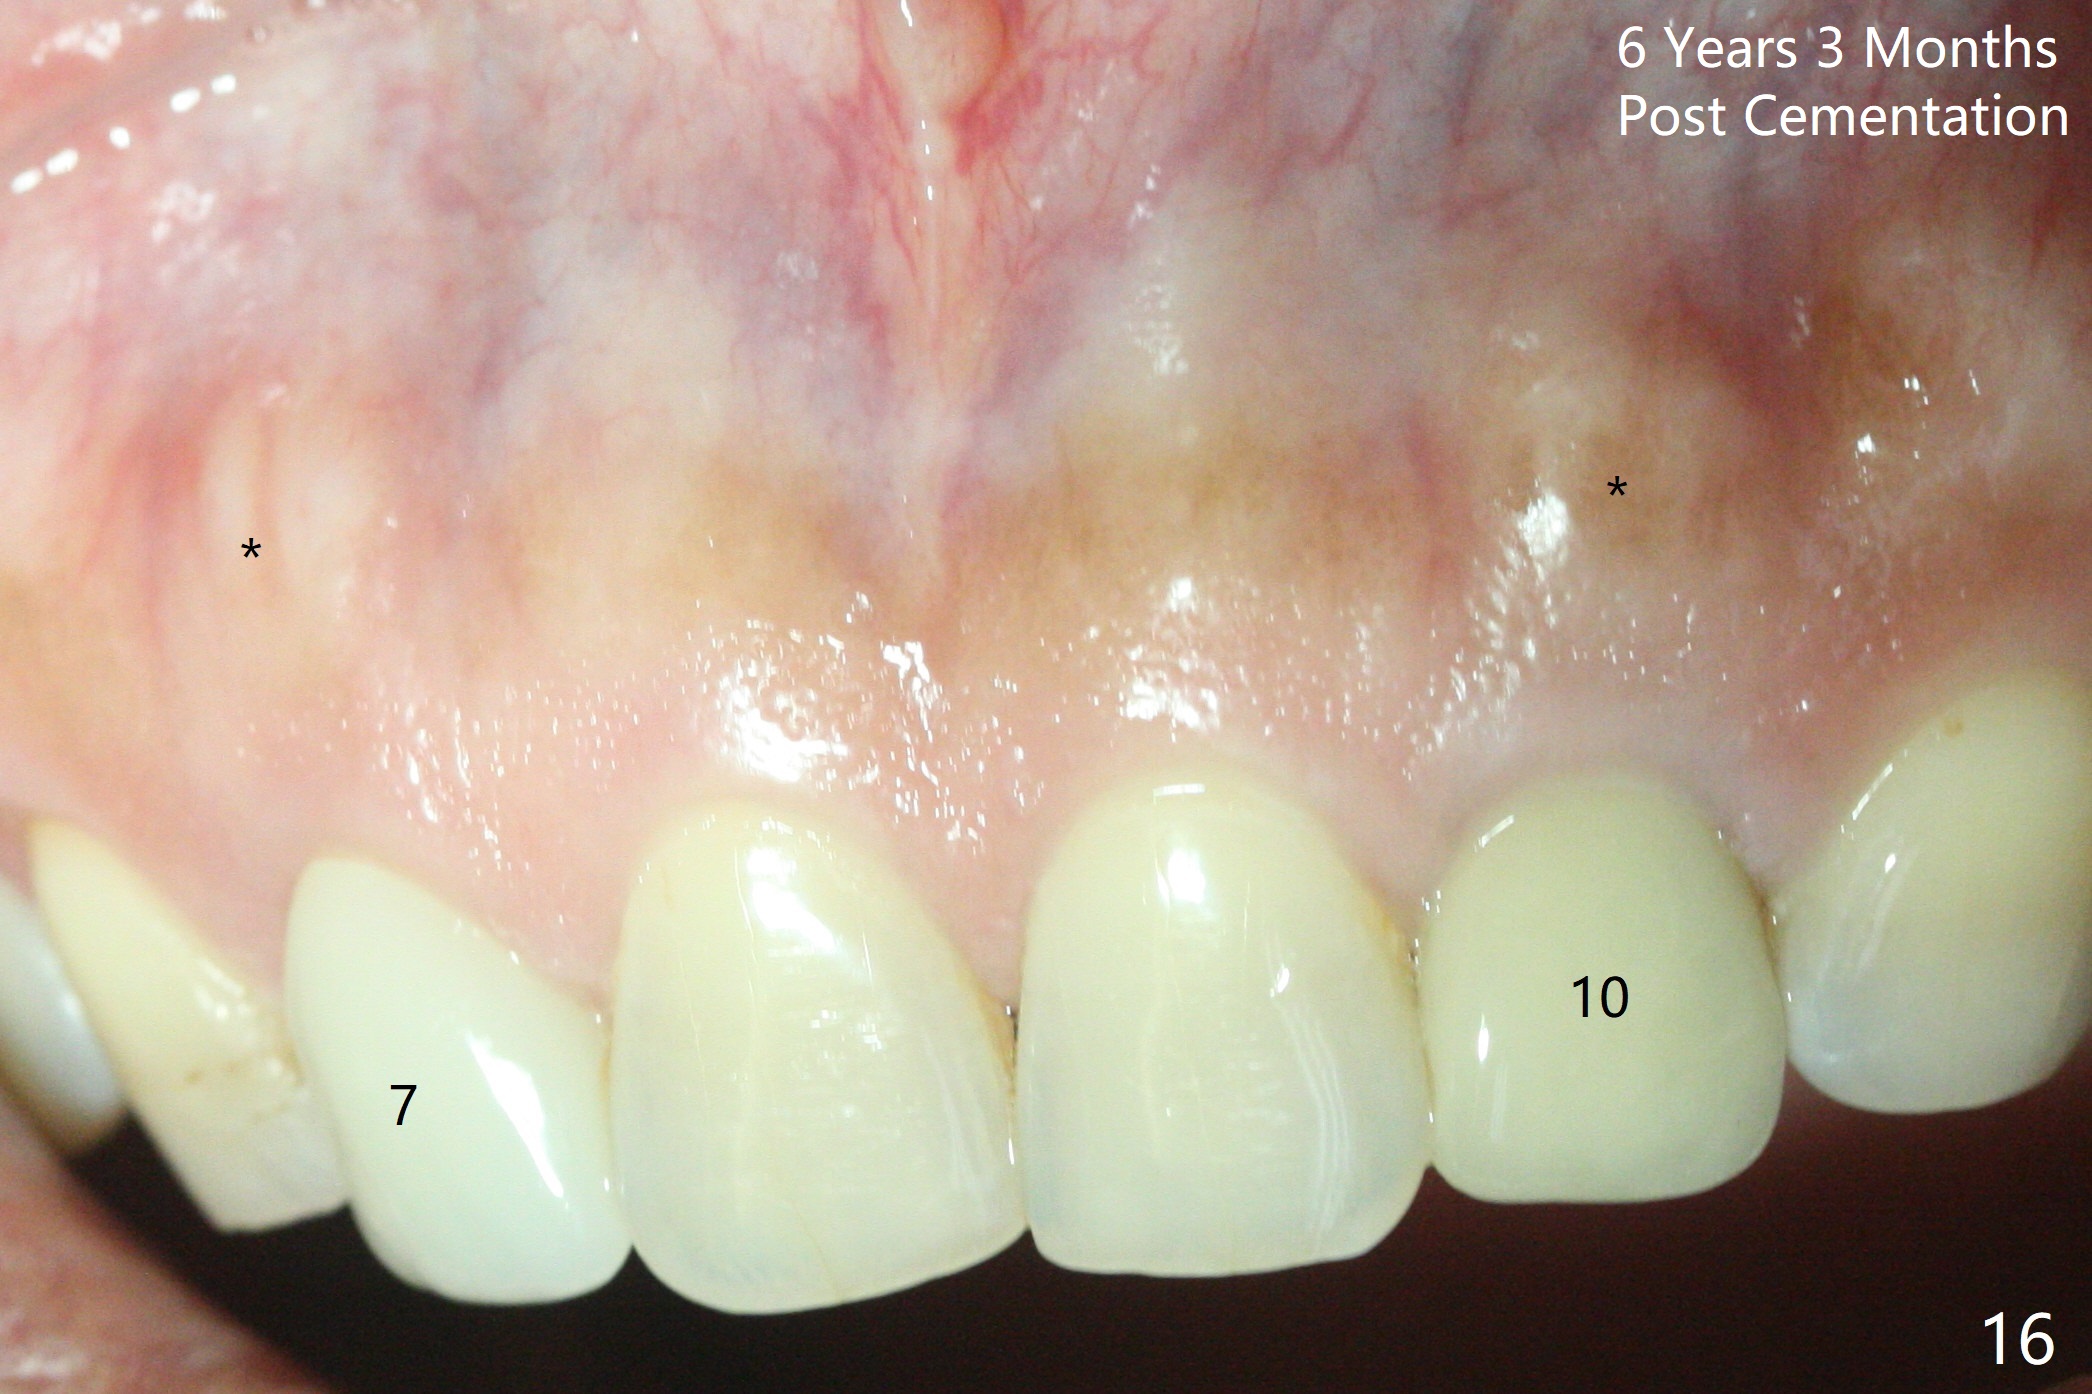

Dense bone forms immediately next to the implant 3 years 5 months post cementation (Fig.13) without gingival recession (Fig.14,15). In fact, the buccal plate maintains root contour over the implant (Fig.15 *). The root prominence remains 6 years 3 months post cementation (Fig.16-18 *). Appreciate the labial concavity associated with implant placement 6 years 9 months post cementation (Fig.19). The implant must have been placed quite palatal.